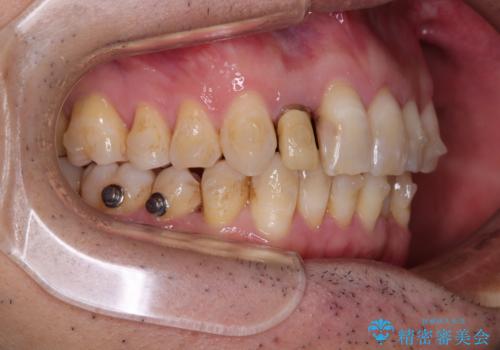

- 前歯のデコボコを気にして来院された患者様です。

目立たない装置で手軽に治したいとのことで、インビザラインにて矯正治療を行うこととしました。

前歯のクラウンは変色が著しいため、矯正治療後にオールセラミッククラウンにて補綴治療を行うこととしました。